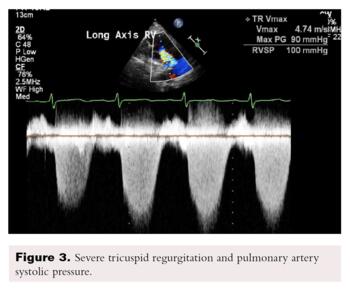

Transthoracic echocardiography showed severe dilated right chambers. There was a large, highly mobile right atrial thrombus (Figure 2), with severe systolic right ventricular dysfunction: severe tricuspid regurgitation and pulmonary artery systolic pressure of 100 mmHg (Figure 3).